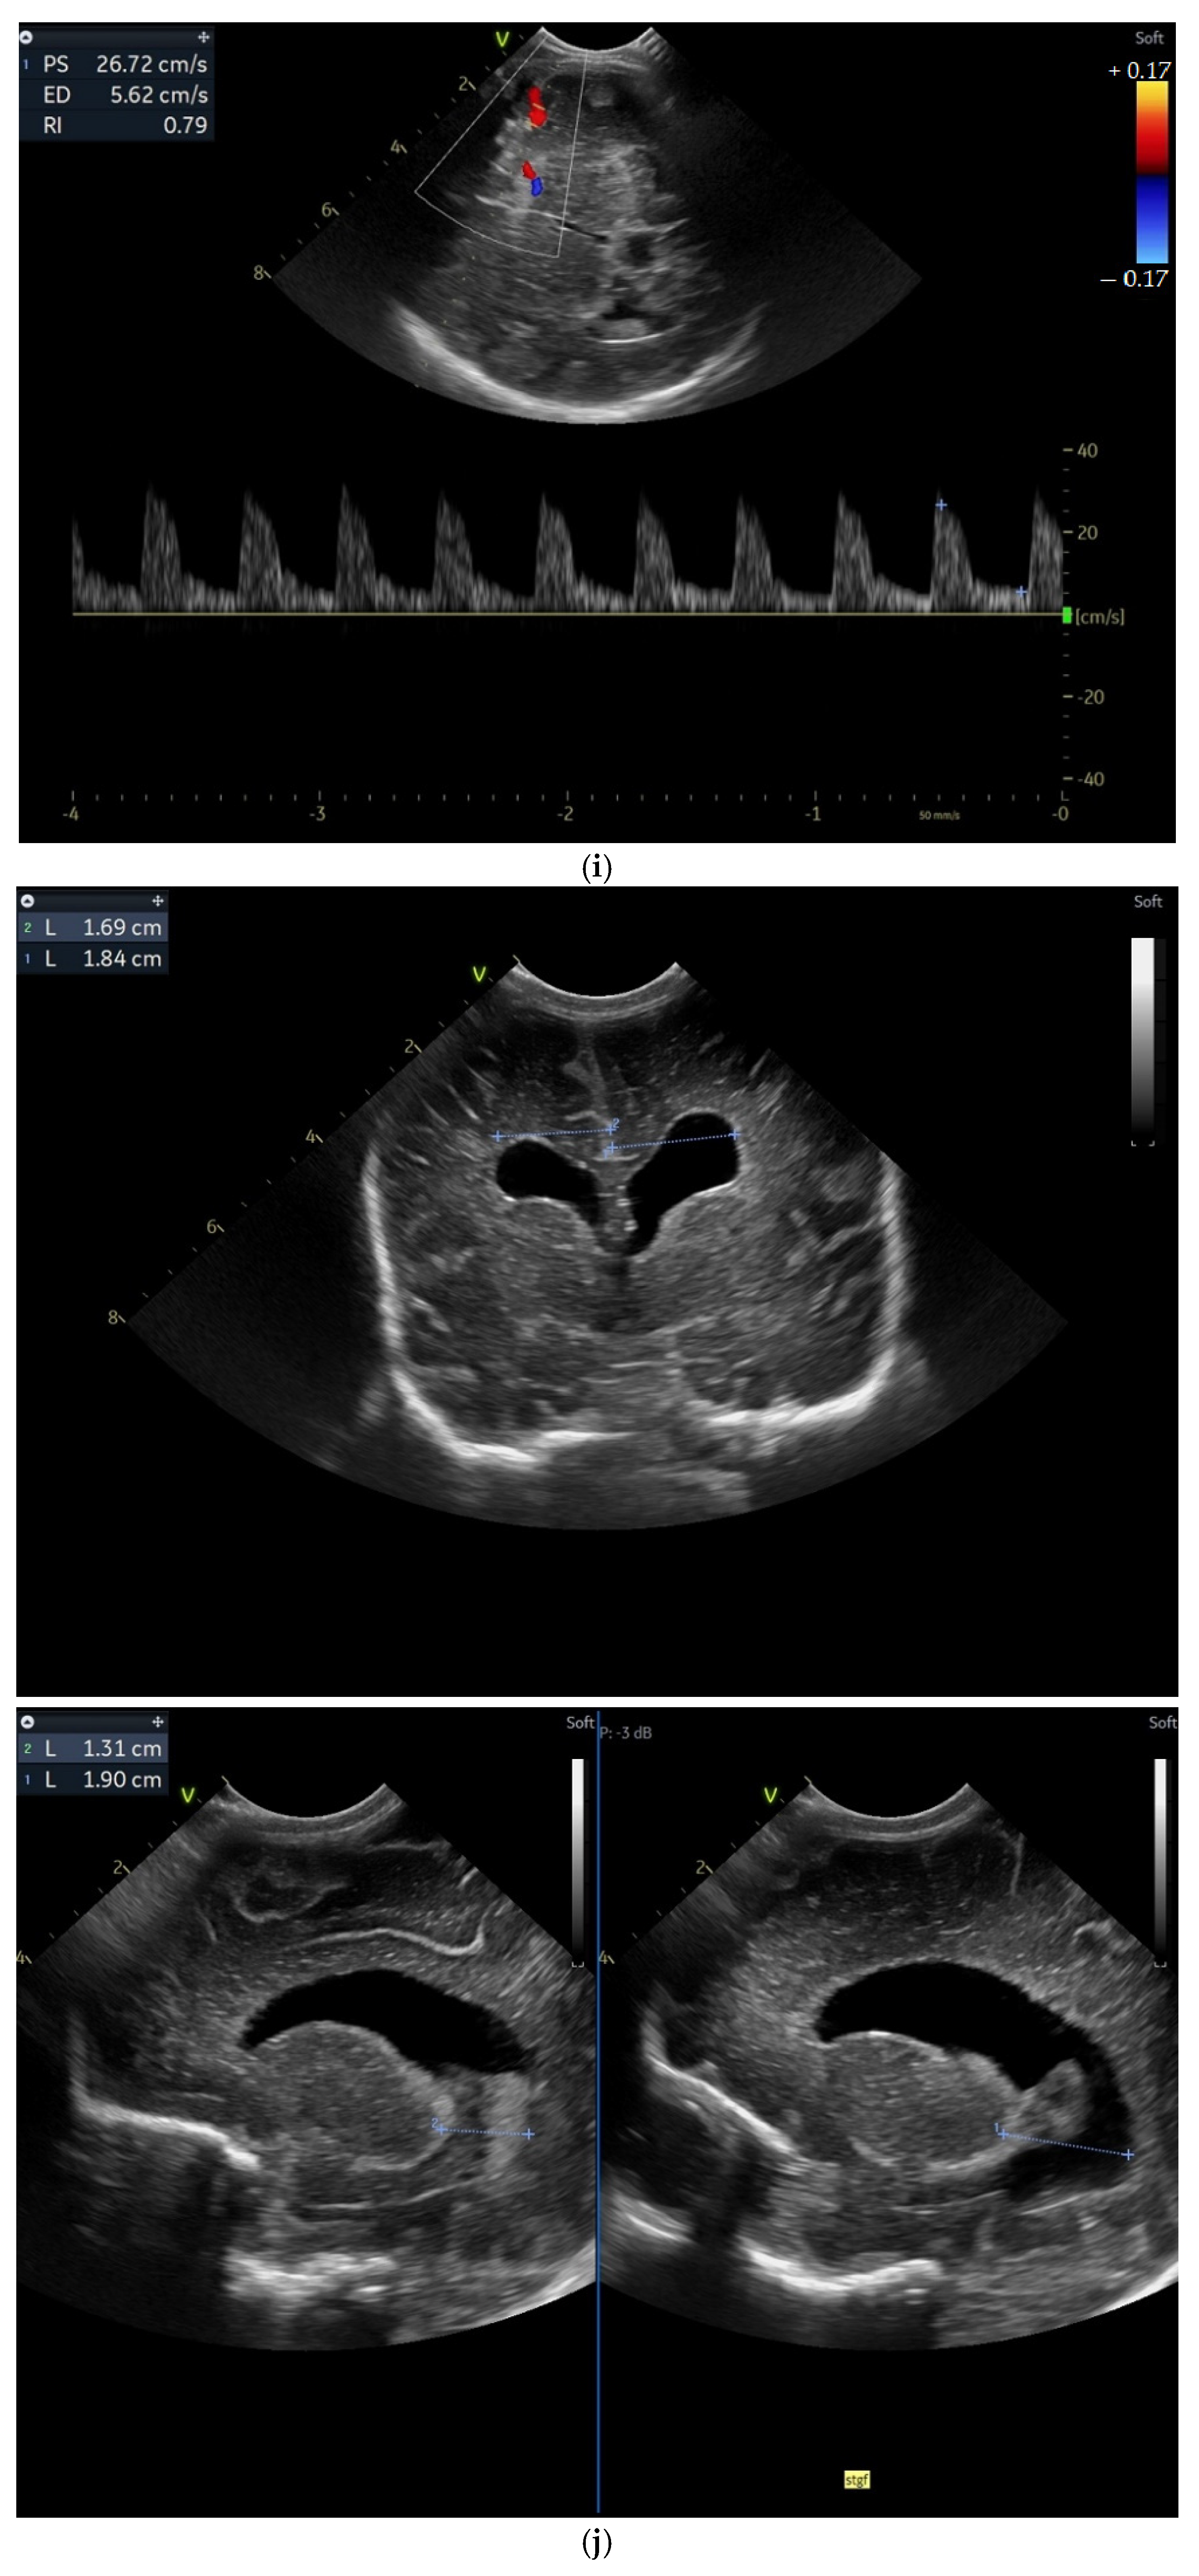

(a) Cranial ultrasound. Coronal view. Enlargement of the lateral ventricles with hyperechoic and third ventricle dilation. D1, D2—Levine index measurement. D3, D4—anterior horn width measurement. D5—third ventricle (personal image collection). (b) Cranial ultrasound. Sagittal view. Up—left ventricle. D1, D2—lateral ventricle measurements and thalamo-occipital horn width. Down—right ventricle. D1, D2—lateral ventricle measurements and thalamo-occipital horn width (personal image collection). (c) Cranial ultrasound. Sagittal view. Up—enlargement of the third and fourth ventricles. Measurements of the ventricles. Down—measurement of the resistive index (RI) performed on the anterior cerebral artery (ACA) using Doppler flow measurements. RI—0.74 (personal image collection). (d) Cranial ultrasound. Transtemporal view. Yellow arrow—enlargement of the Sylvian aqueduct (personal image collection). (e) Cranial ultrasound. Sagittal view. Yellow arrow—arachnoid cyst posterior to the third ventricle (personal image collection). (f) Cranial ultrasound. Coronal view. Lateral ventricles and third ventricle enlargement. D1, D2—Levine index measurement. D3, D6—right lateral ventricle measurement (anterior horn width). D4, D5—left lateral ventricle measurement (anterior horn width) (personal image collection). (g) Cranial ultrasound. Sagittal view. Left—left ventricle. D1—thalamo-occipital distance measurement. Right—right ventricle. D2—thalamo-occipital distance measurement (personal image collection). (h) Cranial ultrasound. Coronal view. Up—orange arrow—third ventricle. Red arrow—fourth ventricles. Yellow arrow—arachnoid cyst. Down—resistive index measured on the anterior cerebral artery. RI—0.79 (personal image collection). (i) Cranial ultrasound. Transversal view. Up—RI precompression value on the middle cerebral artery performed with Doppler examination. RI—68. Down—RI post-compression value on the middle cerebral artery performed with Doppler examination. RI—0.79 (personal image collection). (j) Cranial ultrasound. Up—coronal view. L1, L2—Levine index measurement of the lateral ventricles. Down—sagittal view. L1, L2—measurement of the thalamo-occipital distance (personal image collection). (k) Cranial ultrasound. Sagittal view. L1, L2—measurement of the third ventricle. L3, L4—measurement of the fourth ventricle. L5, L6—measurement of the arachnoid cyst (personal image collection). (l). Head circumference-for-age. “X” symbols represent the measurements performed from birth and follow-up examinations. Head circumference was still under the curve during follow-up examinations (personal image collection) [28].

After discharge, at three weeks after birth (follow-up examination), the ventricle measurements showed wider ventricles and the arachnoid cyst was still present (Figure 3j,k).

The next follow-up examination performed a week later showed a delta-RI of 0.12 and an increase in the cranial perimeter (+ one cm since the last follow-up).